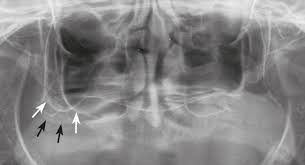

상악(윗턱) 후방부는 오래 치아가 없으면 상악동이 내려오면서

수직으로 임플란트를 넣을 공간이 남지 않는 경우가 많습니다.

신경·상악동 손상 위험이 있거나, 뼈 이식 없이는 원하는 길이 확보 불가.

각도를 활용해 뼈량이 풍부한 부위에 고정. 상악동·신경과 안전 거리 자연스럽게 확보.